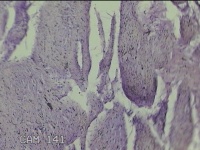

直肠息肉

性别

女

年龄

39岁

临床诊断

混合痔

一般病史

反复肛门肿物3月。

标本名称

大体所见

灰白暗红色条索状肿物5.3x2x0.8cm一个,表面糜烂,切面灰白暗红色,质软。

考虑内痔,伴出血、炎症。